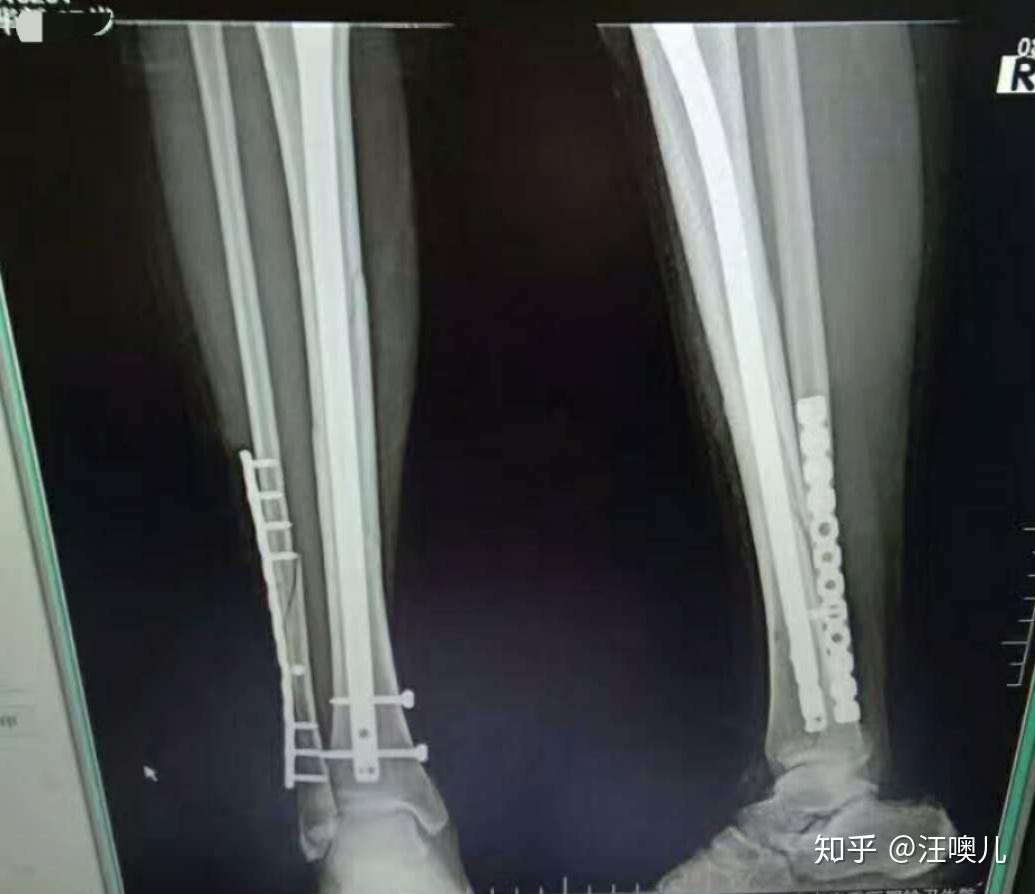

现在是11:57分 我睡了短暂的一觉便自然醒了。 前年过年一天夜晚因为一场小车祸,我右小腿胫腓骨骨折,连夜送去医院,我没有哭,甚至在医生在告知我骨折时我都没有想太多,现在回想起来16岁的我心很大。安钢板的痛我也就不回忆了,说说取钢板吧。 2019.6.21早上8:55分,我躺在了手术台,医生在我注射麻药前把我的右腿抬了起来,和他的助理给我右腿涂满了消炎杀菌水,一瞬间我的腿就变成了黄色,后来注射麻药3秒钟我睡着了。 醒来麻醉消失已经是11:35分,我疼的大哭,尽管我18岁,但我还是没有忍住。 现在我已经是术后第十天,每个夜晚对于我来说都是煎熬,睡着不到1个小时就可能会被疼醒,真的很痛苦。最近每天晚上我都会哭,我怕长期下来我人都会变老。给大家看看部分伤口图吧。 之后再更吧,希望大家一定要注意安全,骨折太痛苦了!!!!! 因为有小伙伴想看一下x片子,我放一张大前年腿受伤刚做完手术有钢板和钉子的片子图,去年取出钢板的片子图没找到啦… 2020.9.27追更 以下图片是我现在恢复一年两个月的样子~ 有什么问题大家可以在 评论,看到都会回复的,祝大家身体健康~ ♀️